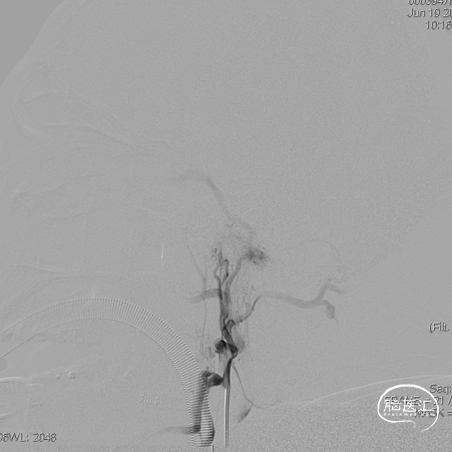

左侧咽升供血的HCDAVF,逆流至海绵窦,经眼上静脉-面静脉引流。

Echelon微导管超选面静脉,后通过眼上静脉超选至海绵窦,进一步超选至瘘口,微导管造影确认在位。

三枚弹簧圈对瘘口进行填塞,后通过Echelon微导管进行缓慢注胶,中途反复确认注胶形态。